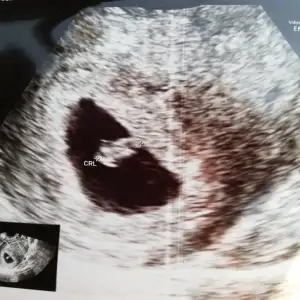

seninki tam sürpriz şoookkk Bir de sen öyle haklıydın ki hani boş gebelik korkusu ve hiç bir şekilde uştrasondan başka bir şekilde anlaşılmıyor.beta düzenli ordan da anlaşılmıyor veeee 2. Ultrasonda şooookkk

Bir de sen öyle haklıydın ki hani boş gebelik korkusu ve hiç bir şekilde uştrasondan başka bir şekilde anlaşılmıyor.beta düzenli ordan da anlaşılmıyor veeee 2. Ultrasonda şooookkk

bende duyarım inşallah kalp atışlarını

bulantı ilacı ne verdi? Valla o kalp atışı hızını sordum bende doktora da efsana dedi